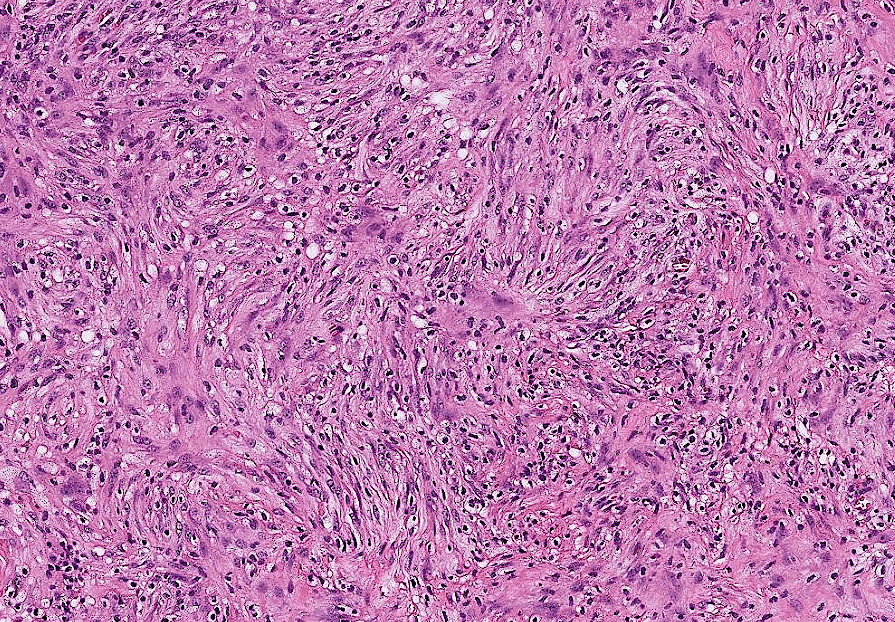

breast cancer

dyslipidemia

hepatocellular carcinoma